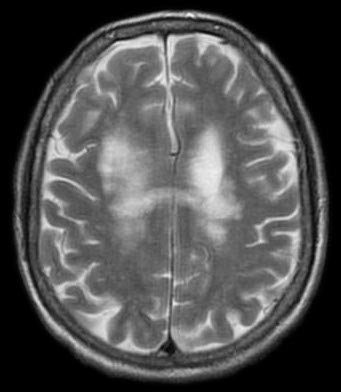

Progresivní multifokální leukoencefalopatie (PML), známá též jako progresivní multifokální leukoencefalitida, je vzácné a obvykle fatální virové onemocnění, které je charakteristické progresivním poškozením (-patie) nebo zánětem bílé hmoty…

Progresivní multifokální leukoencefalopatie (PML) je způsobena reaktivací saprofytického papovaviru.

Progresivní multifokální leukoencefalopatie (PML), známá též jako progresivní multifokální leukoencefalitida, je vzácné a obvykle fatální virové onemocnění, které je charakteristické progresivním poškozením (-patie) nebo zánětem bílé hmoty (leuko-) mozku (-encefalo-) na různých místech (multifokální). Vyskytuje se téměř výhradně u lidí s těžkou imunodeficiencí… Wikipedie